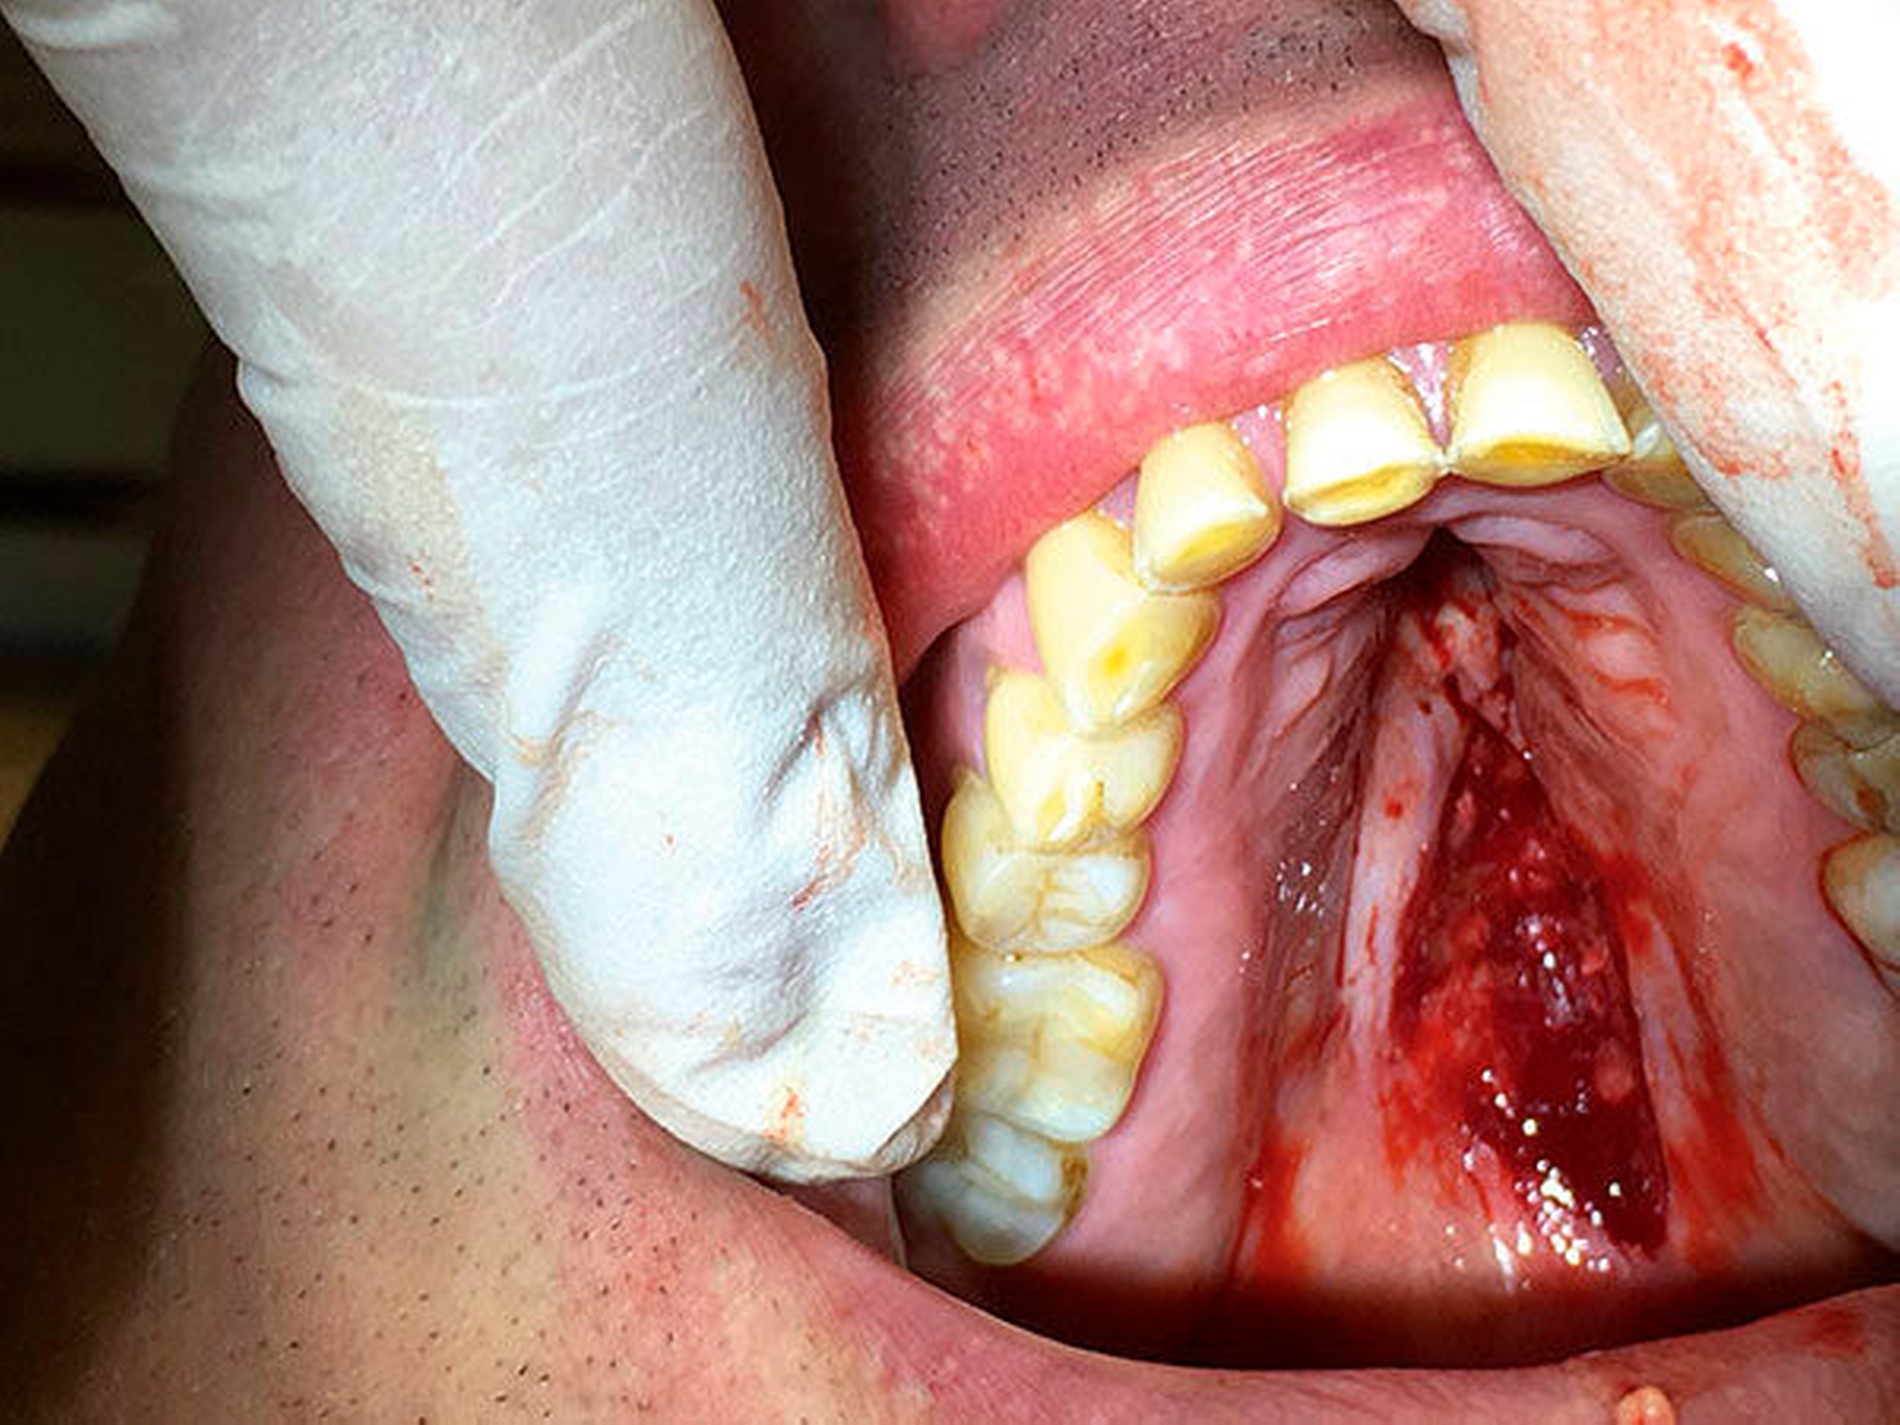

Die digitale Volumentomografie zeigte einen weichgeweblichen Tumor – bei vollständiger Erhaltung der Kontinuität des knöchernen Gaumens. Nach ausführlicher Aufklärung des Patienten wurde die Veränderung mit Verdacht auf ein pleomorphes Adenom in Lokalanästhesie vollständig exzidiert und der pathohistologischen Befundung zugeführt. Postoperativ wurde eine Verbandplatte eingebracht, unter der die Wunde sekundär granulierte. Die Heilung verlief komplikationslos. Nach vier Wochen war die Wunde vollständig epithelialisiert.